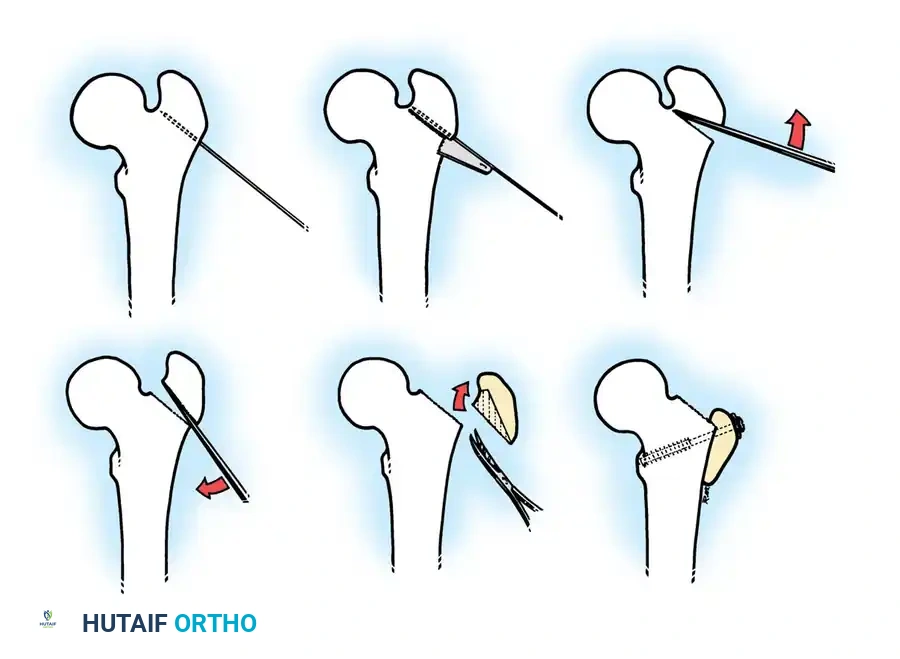

Step-by-Step Surgical Technique:

1. Positioning: The patient is placed supine on a radiolucent Jackson table. A bump is placed under the ipsilateral hip.

2. Approach: A standard lateral approach to the proximal femur is utilized. The fascia lata is incised, and the vastus lateralis is elevated off the intermuscular septum and reflected anteriorly to expose the proximal femoral shaft.

3. Guidewire Placement: Under strict fluoroscopic guidance, a guidewire is advanced into the femoral neck and head, parallel to the planned angle of the blade plate. The goal is typically to achieve a neck-shaft angle of 110 to 115 degrees.

4. Osteotomy: A transverse or closing-wedge osteotomy is performed at the intertrochanteric level using an oscillating saw.

5. Derotation and Varus: The distal fragment is externally rotated (typically 15-20 degrees) to correct the anteversion, and the proximal fragment is allowed to fall into varus.

6. Fixation: A pediatric locking plate or a fixed-angle blade plate is impacted into the proximal fragment and secured to the distal shaft with cortical screws. Compression is applied across the osteotomy site.